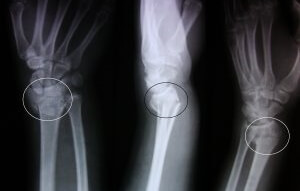

Повреждение руки без смещения

При приземлении на кисть мышцы не оказывают натиска на луч, поэтому его фрагменты не смещаются. На рентгеновском снимке видна только трещина.